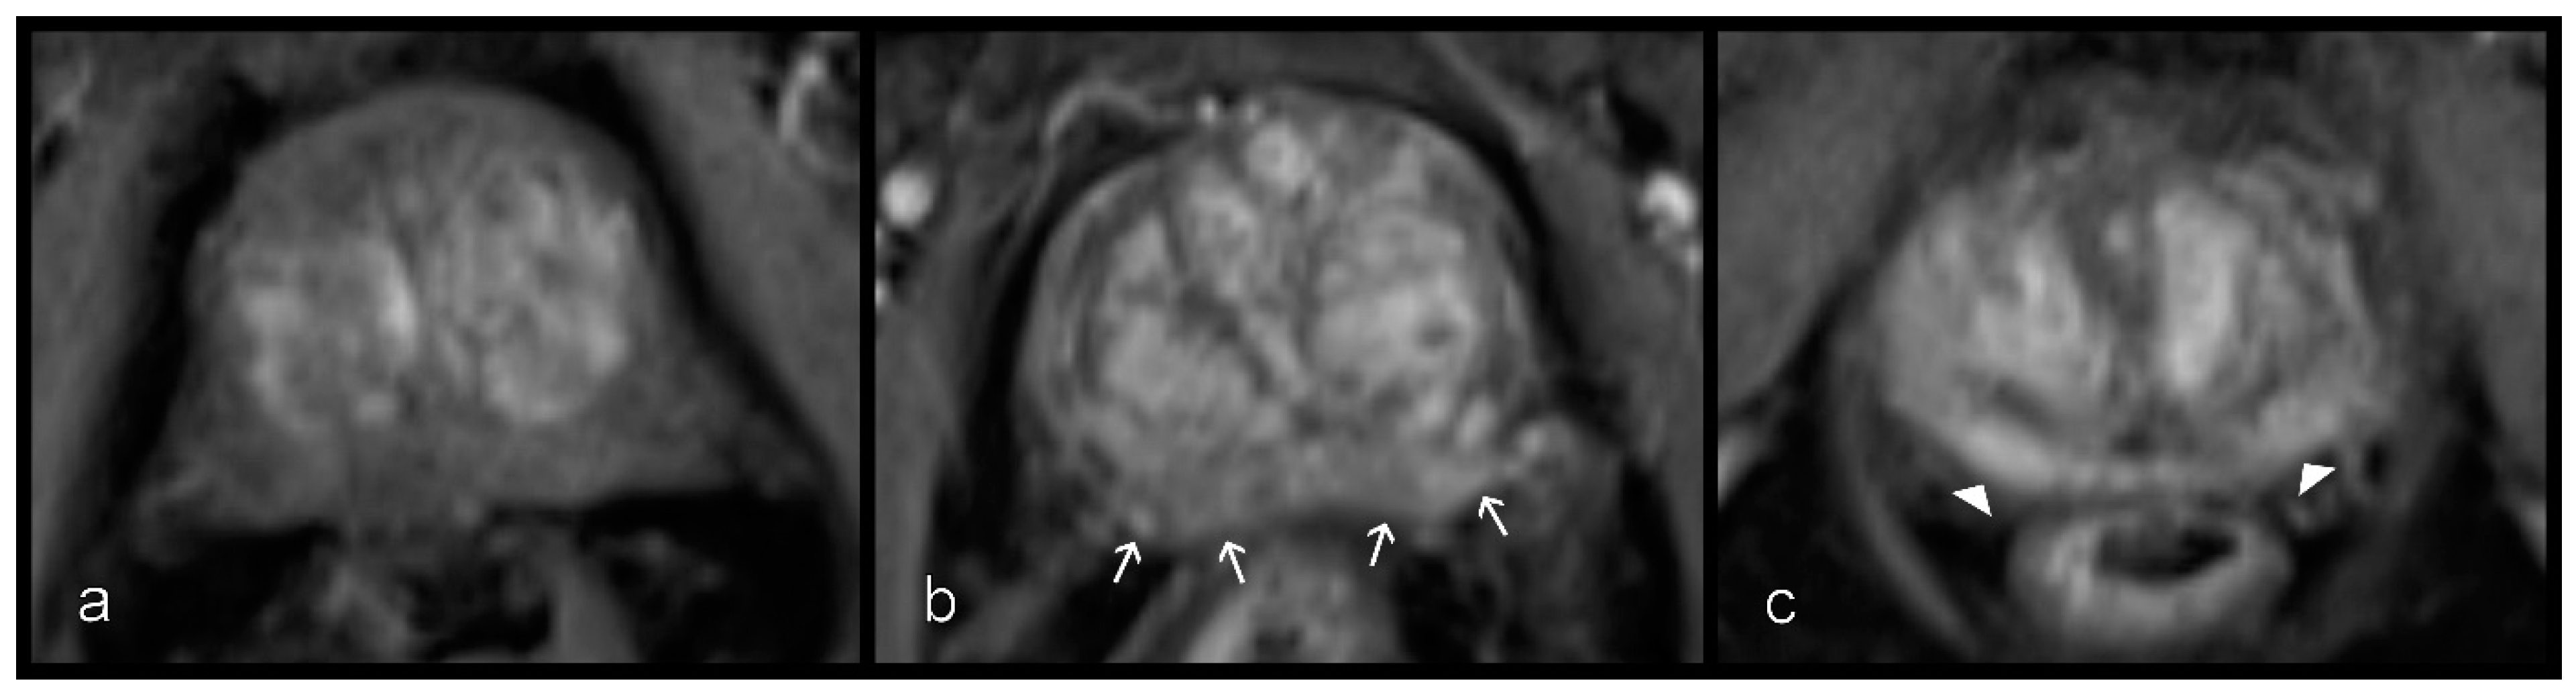

Figure 4.

Different levels of enhancement on contrast-enhanced csVIBE sequences in the peripheral zone. (a) No, (b) mild (white arrows), and (c) severe and early enhancement (arrowheads). No and mild enhancement were combined. csVIBE, native T1 and prototypical dynamic T1 gradient echo sequence.